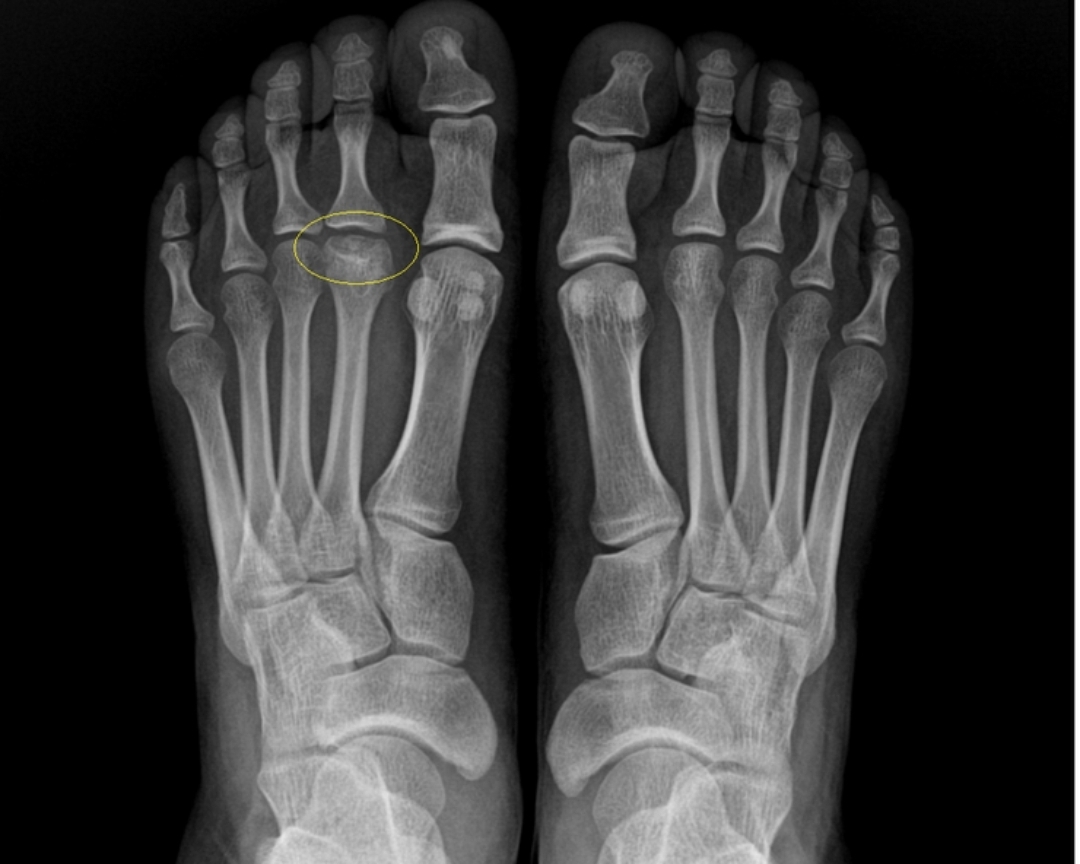

프라이버그병은 발의 중족골두(metatarsal head), 주로 두 번째 중족골두에 발생하는 드문 질환입니다. 중족골두는 발가락과 연결되는 발바닥 앞쪽의 둥근 뼈 끝부분입니다.

* 주요 특징: 중족골두의 혈액 공급이 손상되면서 뼈 조직이 괴사하고, 이로 인해 중족골두의 모양이 납작해지거나(편평화), 변형되어 관절염(골관절염)으로 이어질 수 있습니다.

* 주요 발생 부위: 대부분 두 번째 중족골두에서 발생하며, 드물게 세 번째 등 다른 중족골두에도 나타날 수 있습니다.